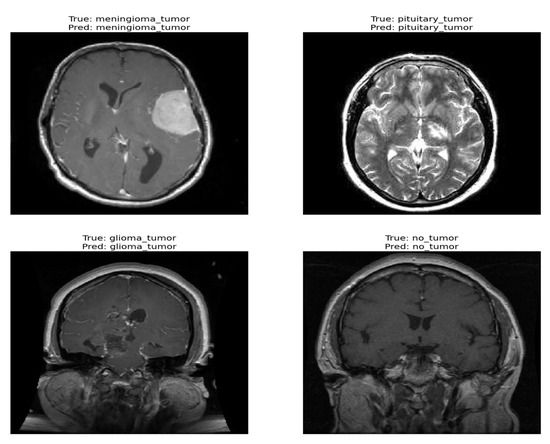

The confusion matrix was utilized to provide additional insights into the model’s performance by summarizing the correctly and incorrectly classified instances. For the validation set of 857 images, the model correctly identified 841 images, while 16 images were misclassified as shown in Figure 4. Furthermore, Figure 5 and Figure 6 present the classification outcomes of the proposed study, illustrating both accurate and inaccurate classifications.

Figure 5.

Correct classification result of proposed ViT model.

Figure 5 and Figure 6 present the visual results obtained from our FT-ViT model. These figures serve as compelling evidence of the model’s efficacy in accurately classifying different tumor types. As depicted in Figure 5, the proposed FT-ViT model exhibits remarkable performance, achieving an impressive accuracy of 98.13%. The high accuracy underscores the model’s capability to correctly identify tumor types with exceptional precision. However, there are instances where the FT-ViT model encounters challenges in accurately classifying tumor types. These instances are also reflected in the confusion matrix, which highlights the cases where the model misclassified tumor types. Figure 6 provides a visual representation of the results where the FT-ViT model encountered difficulties and failed to identify certain tumors accurately. The incorporation of both Figure 5 and Figure 6 allows us to comprehensively evaluate the FT-ViT model, highlighting its overall success in tumor classification, while also shedding light on areas for improvement.